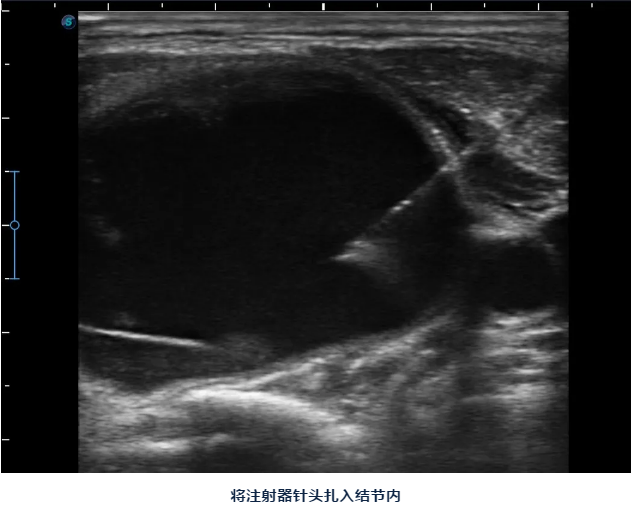

陈主任告诉她:对良性甲状腺结节,现在可以做微创消融治疗,只要局部麻醉,将一根消融针插入结节,通过消融针产生高温就可以将结节灭活,之后结节就会慢慢吸收、缩小。

陈主任说:甲状腺结节消融做完后脖子上只有一个针眼,术后也不影响活动、进食,同时手术是在超声引导下进行,只消融结节,能尽最大限度保护正常甲状腺组织,也可以清楚避开血管、气管、食管、神经等周边组织器官,术后出现声音嘶哑、出血、甲减的几率要小很多。